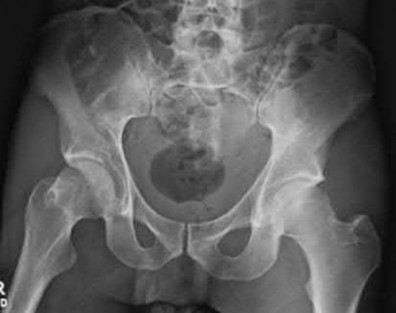

Question 2:

A 12-year-old boy presents with left thigh pain, an antalgic gait, and an externally rotated left lower extremity. Radiographs demonstrate the pathology shown. Which of the following is considered an absolute indication for prophylactic pinning of the asymptomatic, contralateral hip in a patient presenting with Slipped Capital Femoral Epiphysis (SCFE)?

Correct Answer: Underlying endocrine disorder (e.g., hypothyroidism)

Explanation:

SCFE is characterized by a displacement of the proximal femoral epiphysis. Prophylactic pinning of the contralateral hip is somewhat controversial but generally recommended in patients with a high risk of subsequent contralateral slip. Absolute indications or highly strong recommendations for prophylactic contralateral pinning include an underlying endocrine disorder (such as hypothyroidism or growth hormone deficiency), renal osteodystrophy, previous radiation therapy, and presentation at a very young age (e.g., < 10 years). Endocrine disorders dramatically increase the risk of bilateral involvement, often occurring simultaneously or sequentially.